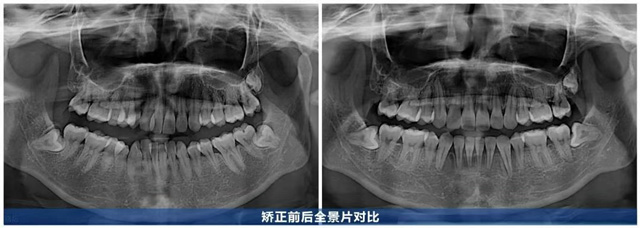

历时2年,何女士的牙齿焕然一新:曾经拥挤的牙齿排列有序,前牙深覆合改善,咬合关系恢复正常,笑起来牙弓弧度流畅自然,笑容更舒展了。从正面看,牙齿排列与唇形勾勒出协调的“微笑曲线”,上前牙显露量恰到好处,牙龈几乎不外露,面部线条更柔和,笑容也更显柔和自信。